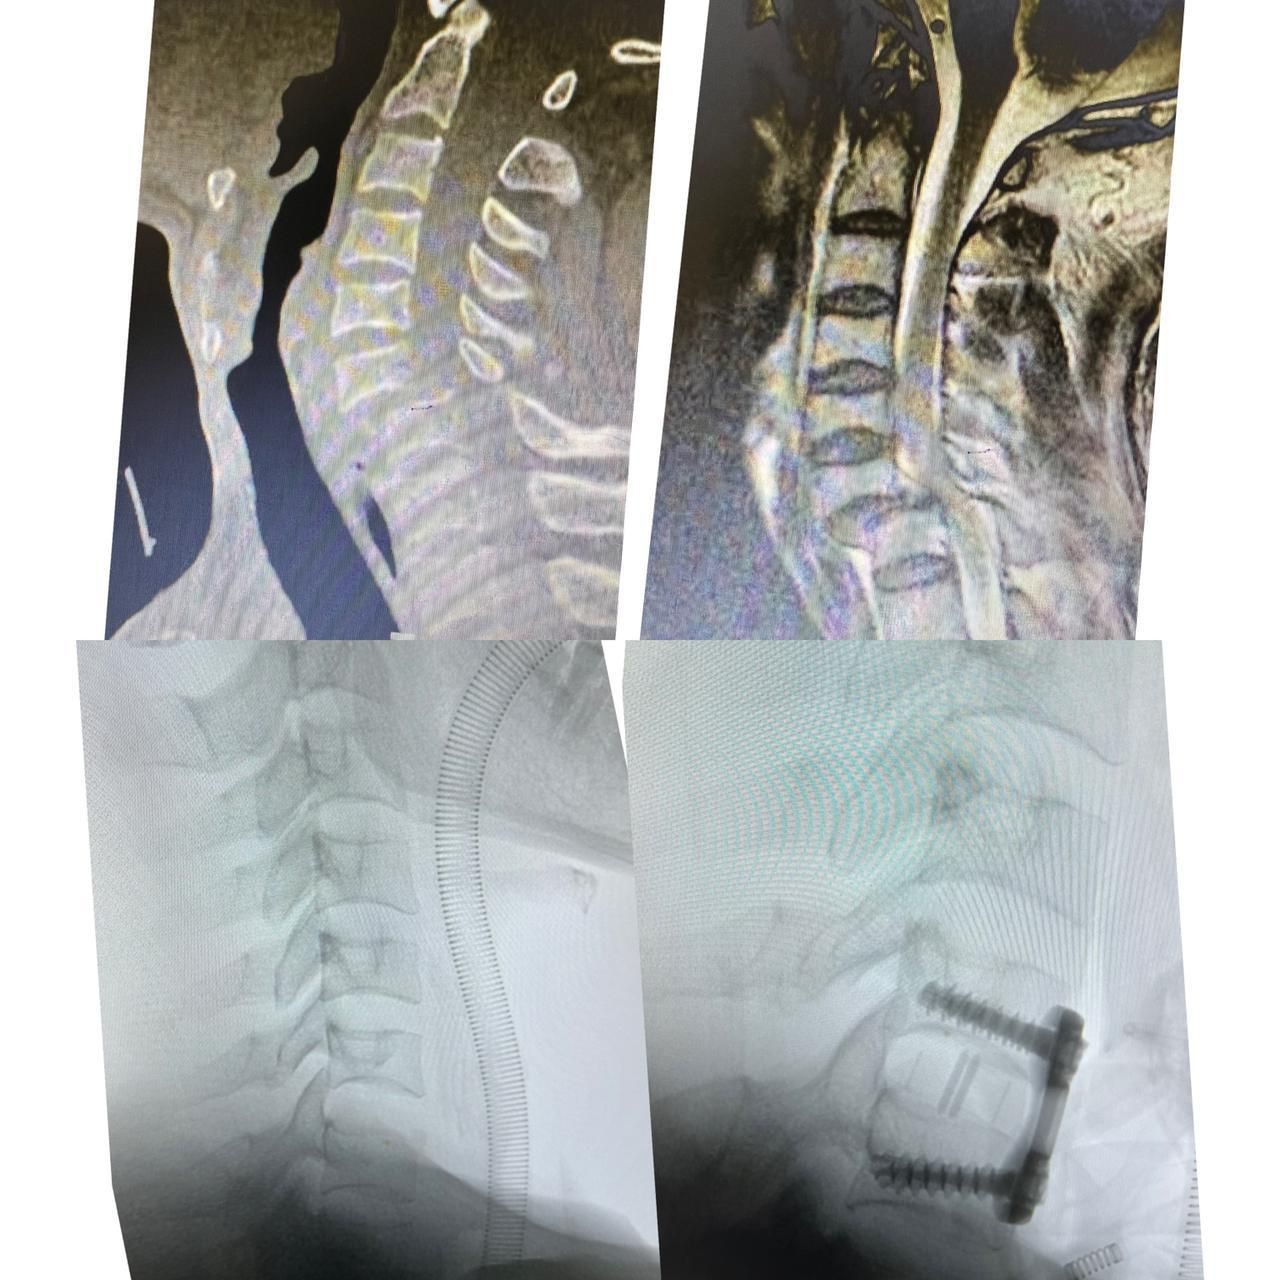

وأوضح الفريق الطبي المعالج ان المريض كان قد وصل لطواريء المستشفى بعد اصابته في حادث مروري  أدى الى اصابته لخلع كامل للفقرة العنقية السادسة والسابعة مع ضغط كامل للحبل الشوكي مما سبب شلل رباعي كامل للاطراف.

هذا وقد قام اطباء العظام المختصين بمستشفى الملك فهد  وعلى الفور وفي وقت وجيز من تجهيز المريض لغرفة العمليات بعد ان عمل له اشعة الرنين المغناطيسي والفحوص اللازمة حيث اجريت له عملية جراحية عاجلة لمنع حصول شلل دائم  للمريض.

وقد تم ارجاع خلع الفقرات العنقية  وتحرير الحبل الشوكي وتثبيت الفقرات والمتابعة للمريض بعد نقله للعناية المركزة.

ومن جهة ثانية وذات السياق ابدى المريض تحسنا كبيرا في حركة الاطراف العلوية والسفلية  اضافة الى التاهيل الطبي له حتى رجوعه الى حالته الطبيعية باذن الله تعالى.